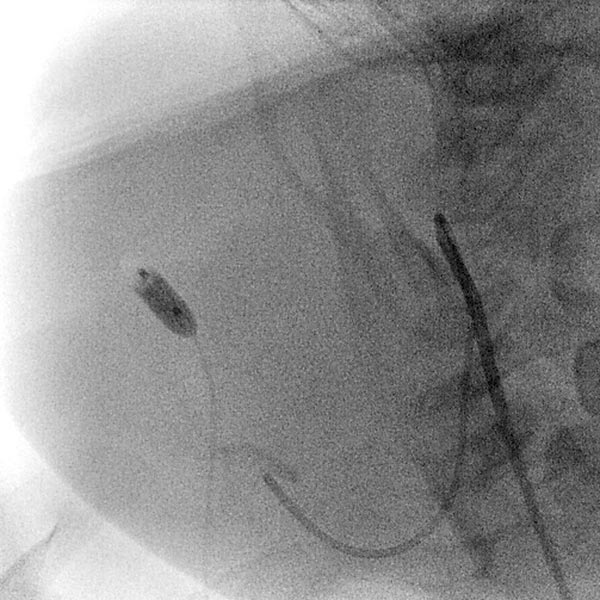

In view of the lack of regression, probably also caused by the relevant stenosis of the venous outflow, the decision to embolize the hemangioma was made in the 24th month of life in order to induce regression of the mass. In a first step during intervention, the venous outflow (right external jugular vein) was cannulated retrogradely from transvenously.

A small balloon catheter was then inserted to block the venous outflow prior to embolization to prevent unintended dislocation of the arterially injected embolic agent to the venous side.

Digital subtraction angiography (DSA) after injection into the right common carotid artery shows the infantile hemangioma mainly supplied from the external carotid artery, as expected.

Digital subtraction angiography (DSA): After insertion of a 4F diagnostic catheter transarterially into the external carotid artery, selective advancement of a microcatheter into the maxillary artery. The infantile hemangioma presents as typical contrast pooling (“tumor blush”). The transvenously inserted balloon blocks the venous outflow and is clearly visible. Embolization was then carried out with particles of 150 micron size and without unintended venous outflow.